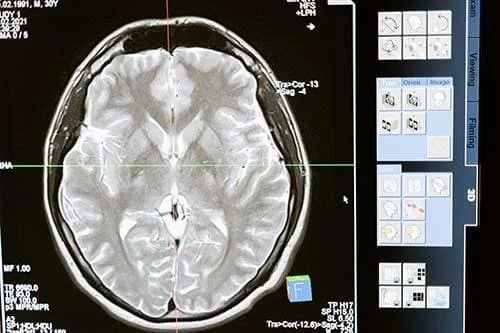

As the brain's most sought-after resource, oxygen fuels its ceaseless activity. Even though only a fraction of the brain's capacity is active at any given time, nearly all the oxygen delivered is harnessed. This oxygen nourishes different brain regions, adapting as needed to perform tasks, particularly during multitasking endeavors. Innovative technology, such as functional magnetic resonance tomography (fMRI), unveils these shifts in blood perfusion that accompany varying tasks.